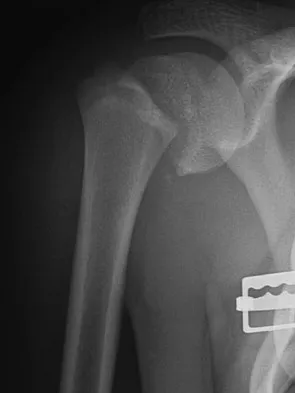

Figures 10a and 10b show the radiographs of a 47-year-old man who reports pain in both shoulders. He has a history of leukemia that was treated with chemotherapy and high-dose cortisone. What is the most reliable treatment option for pain relief in this patient?

Explanation

The radiographs reveal osteonecrosis with collapse. The most reliable and durable treatment for osteonecrosis of the humeral head remains prosthetic shoulder arthroplasty. Osteonecrosis of the humeral head may be seen after the use of steroids, and there is an increasing demand for shoulder arthroplasty in young people because of the use of high-dose steroids in chemotherapy regimes for the treatment of malignant tumors. The indications for most shoulder arthrodeses today include posttraumatic brachial plexus injury, paralytic disorders in infancy, insufficiency of the deltoid muscle and rotator cuff, chronic infection, failed revision arthroplasty, severe refractory instability, and bone deficiency following resection of a tumor in the proximal aspect of the humerus. Clearly, the role of arthroscopy and related minimally invasive techniques in the treatment of humeral head osteonecrosis remains unknown. Hasan SS, Romeo AA: Nontraumatic osteonecrosis of the humeral head. J Shoulder Elbow Surg 2002;11:281-298. Hattrup SJ: Indications, technique, and results of shoulder arthroplasty in osteonecrosis. Orthop Clin North Am 1998;29:445-451.